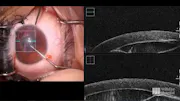

Christopher J. Rapuano, MD, Director of Cornea Service at Wills Eye Hospital, walks through a complicated case in which a 73-year-old woman presented with pseudophakic bullous keratopathy. He explains his initial surgical plan and shares video to highlight intraoperative complications he encountered with an anterior chamber IOL. Dr. Rapuano then describes how he approached these problems and provided a positive outcome for the patient. To learn more, visit Wills Eye Knowledge Portal